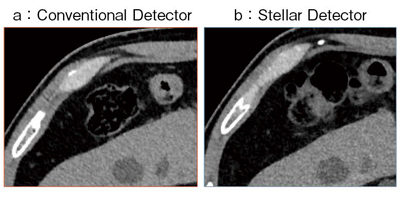

同一患者の腹部単純CT画像を,Stellar Detectorの搭載前と搭載後で比較すると,一見してその違いはそれほど明確ではない。しかし,拡大してみると,例えば腹腔内の脂肪と腹壁の境界では,従来のdetectorの画像は粗くギザギザが目立つが,Stellar Detectorではシャープな境界線として描出される(図1)。肝臓や脾臓を拡大しても,やはりStellar Detectorの方が辺縁がすっきりと見えるようになった。

また,肝実質も,従来のdetectorの画像にはストリークアーチファクト様のノイズが入っているが,Stellar Detectorでは細かな粒状のノイズになっている。

図1 Conventional Detector(a)とStellar Detector(b)の

拡大画像の比較